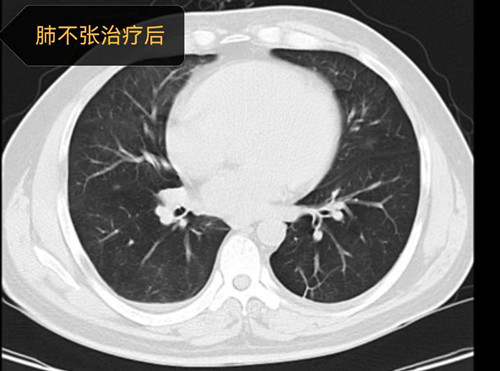

一周后,曾先生生命体征逐渐趋于平稳,神志也逐渐清醒,但吸氧浓度仍较高,超过60%氧浓度,复查肺部CT显示双下肺仍有大片不张。进入下一阶段的撤机拔管环节,呼吸治疗师曾娟利每为其评估肺和膈肌功能,实施肺复张及肺康复,逐步降低各项呼吸机支持参数。经过呼吸三科团队的有效综合治疗,曾先生吸氧浓度有下降,床旁肺部超声提示肺不张明显有改善,几天后曾先生成功脱离有创呼吸机、拔除气管导管,延续无创呼吸机治疗,出院前复查胸部CT,显示肺已完全膨胀开,肺部感染已基本控制。曾先生一路闯过了呼吸衰竭、重症感染、休克、困难脱机、机体康复等重重难关,恢复自理能力,顺利康复出院。出院前杨欢副主医生为其进行健康宣教、戒烟、规范用药和无创呼吸机治疗。